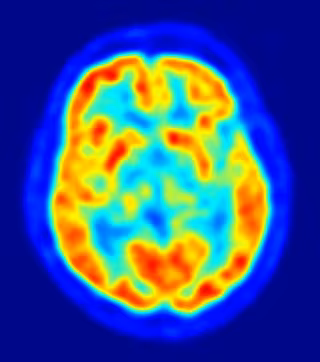

cerebro, recurso, neuronas

Investigadores del Centro de Circuitos Neurales Genéticos RIKEN-MIT han descubierto cómo las células cerebrales pueden recordar nuevos recuerdos y, al mismo tiempo, mantener los antiguos. Según los científicos, las neuronas específicas de una región del cerebro, llamada giro dentado, sirven distintas funciones en la formación de la memoria, dependiendo de si las células madre neurales que las produjeron eran jóvenes, o de edad avanzada.